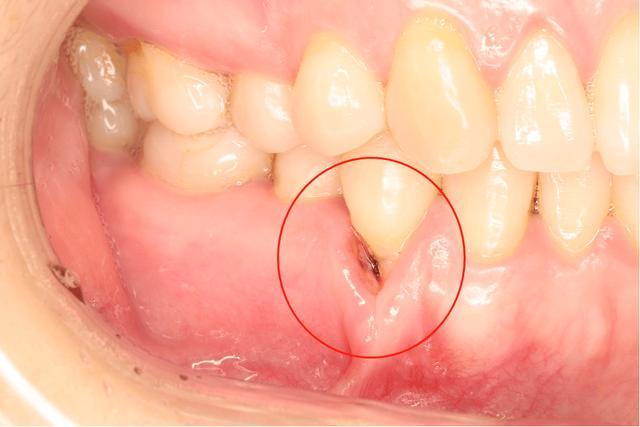

牙周炎的癥狀

1、牙齦紅腫:牙周炎患者的牙齦組織通常會(huì)變得紅腫。

2、牙齦出血:刷牙或咬硬物時(shí)容易出血。